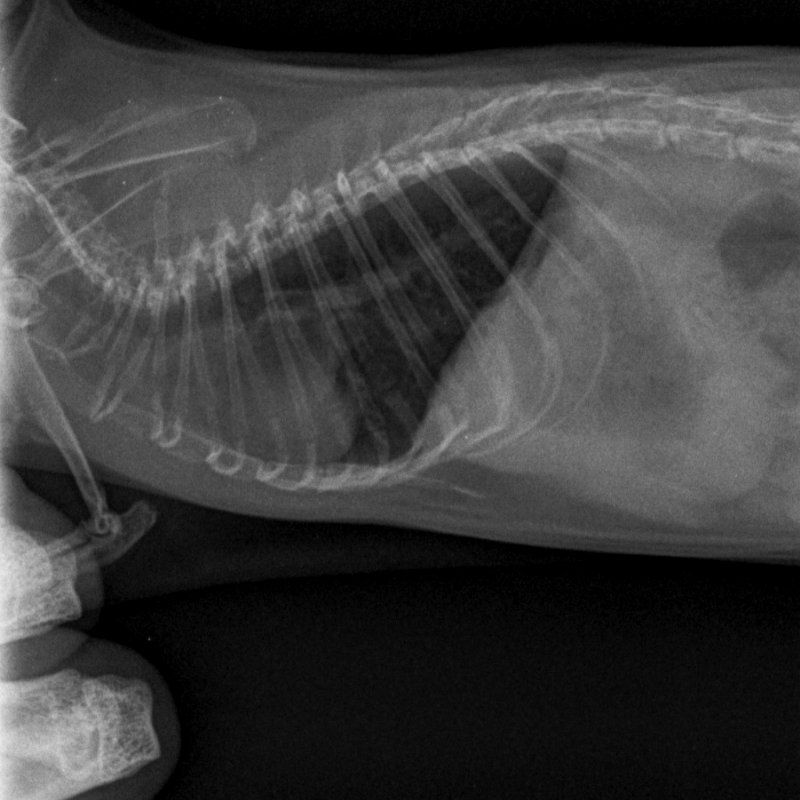

Début avril, comme vu plus tôt, 10 jours de doxycycline, 5mg/kg/12h, en PO pour Koba suite à symptômes respis avec perte de poids.

Il y avait du mieux donc on a arrêté au bout de 10 jours.

Et puis fin avril sa respiration est devenue accélérée de façon flagrante, avec quelques rares bruits respiratoires.

On est repartis sur un mois (28 jours ajd) de doxycycline, toujours à 5mg/kg/12h en PO (bon, pour compenser les risques de perte, on était plus sur du 6mg/kg).

Nouvelle radio ajd. Toujours un peu d'opacité pulmonaire mais le vétérinaire trouve qu'il y a un léger mieux. La radio est pas de qualité top (l'ASV devait me bloquer un créneau long pour qu'il ait le temps de faire la radio, au final ça n'a pas été fait, donc sur 20 minutes avec la clinique + le recap + la radio, ça a du être fait un peu rapidement). Le poids est stable, à 445g environ. Il mange très bien, la respiration est toujours un peu plus rapide mais je la trouve mieux que lorsqu'on a commencé à s'inquiéter.

1733451997_NAC-THORAXPROFIL-25_05_2022-16_01_59-62.JPEG.555773f7acdefce2cbb10126fa361473.JPEG1361081938_NAC-THORAXPROFIL-25_05_2022-16_01_58-547.JPEG.ebf5c5f937890f4f860193d5e7a505d4.JPEG